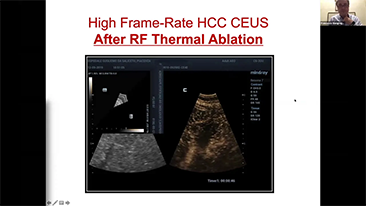

ImĂĄgenes generales

Las soluciones de imĂĄgenes generales de Resona de Mindray ayudan al personal clĂnico a realizar diagnĂłsticos y obtener resultados de tratamiento mĂĄs precisos y eficientes a travĂ©s de sondas para aplicaciones de subdivisiĂłn integrales y herramientas de aplicaciĂłn clĂnica eficientes.